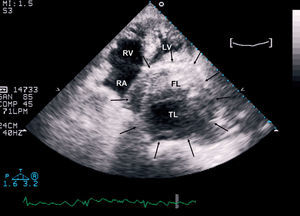

Nine years later the patient was readmitted to hospital due to acute chest pain. The image studies (Figure 1) showed an extremely dilated and tortuous descending thoracic aorta. In agreement with the patient and family, it was decided to maintain a conservative attitude. A few hours after his admission, the patient experienced a new episode of chest pain associated with severe persistent hypotension. A transthoracic echocardiogram was performed (Figure 2), which showed severe dilatation of the descending aorta (with a maximum aortic diameter of 108×95 mm), as well as a chronic residual dissection, with a flap separating the true lumen from a crescent-shaped thrombosed false lumen in the transversal views. The echocardiogram also revealed that the descending aorta was compressing and completely obliterating the left atrium (Figure 2). The patient died not long after.

Figure 2. Transthoracic echocardiogram (apical 4-chamber view) showing a giant aneurysm of the descending thoracic aorta (arrows) causing the collapse of the left atrium. Note the chronic dissection with the intimal flap separating a true lumen (TL) from a crescent-shaped thrombosed false lumen (FL). RA indicates right atrium; RV, right ventricle; LV, left ventricle.